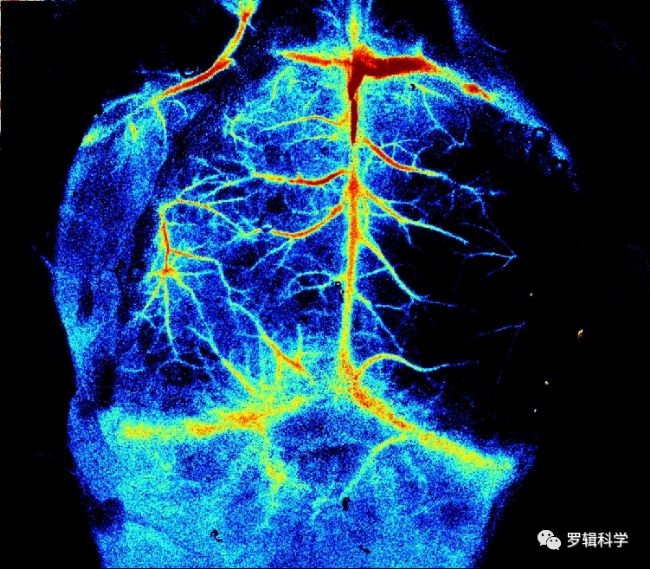

3-1激光微循環三維介觀成像技術

可對生物樣品進行活體微循環血管三維成像,具有無標記、非接觸、無創無損的技術特點,同時深度可達5mm以上、分辨率可達2um以內,通過類激光共聚焦的雙振鏡掃描及時間序列成像,可以快速采集連續時間序列的活體微循環血管的三維影像結果,并可分析得到血管直徑、密度、分支數量等精確定量結果。在腦、皮膚和微循環血管研究,眼視覺疾病研究,微小動物生長發育研究,及生物材料、生物膜研究等領域具有廣闊的應用前景。

3-2激光微循環功能成像技術

新一代HR-LSCI激光微循環功能成像技術,以獨有的無標記、非接觸、高分辨、全視場快速成像的技術優勢,為生命科學和臨床醫學研究提供一種全新有效的微循環血流功能成像的手段;該系統可實時觀察全局、局部及單根微細血管的血流灌注與分布及血管形態等相對變化。

⼩⿏MCAO腦缺⾎造模觀察